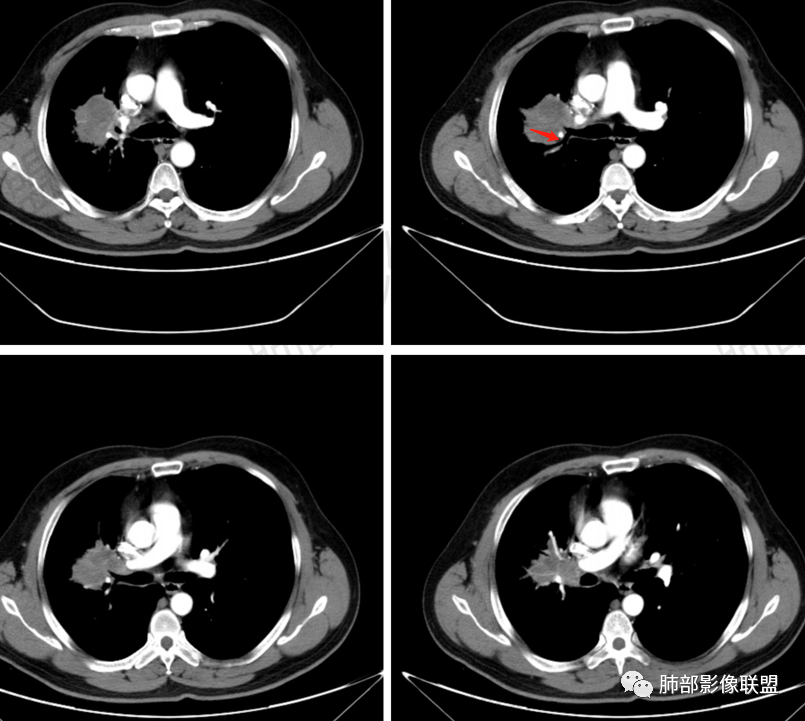

前段支气管鼠尾状狭窄,壁增厚

尖段/后段支气管受压推移

多发树芽,病灶边缘模糊的GGO

环形强化

坏死区几乎是寸草不生

纵隔淋巴结肿大并不明显,就这一个肿大较明显,但仍呈椭圆形,中心少许坏死。

1、坏死区内寸草不生;2、病灶环形强化;3、远端树芽和结节;4、远端不是阻塞性炎症,而是树芽和结节,右肺上叶前后段都有,后段为主,而堵塞的支气管应该是前段;这些树芽的位置不是堵塞支气管的责任区;5、支气管不是突然截断堵塞,而是逐渐狭窄;6、纵隔淋巴结是椭圆形增大,内有坏死,不是肿瘤的圆形饱满;7、支气管周围粘液样坏死,符合仙人掌结核改变;

2、湖泊样坏死:这个病例其实不是湖泊样坏死。湖泊样坏死边界不清,周围有水草样改变;这个病例的坏死更像水库,不是湖泊,坏死区边界清楚,里面寸草不生;

水库:是人工的,边缘是石头彻的大坝(环形强化类似大坝),坝缘没草长,边界清楚。

湖泊:是天然的,周围没有环形强化的大坝,是逐渐过渡到强化区的,边缘可有细小血管或者坏死不彻底的肿瘤区。